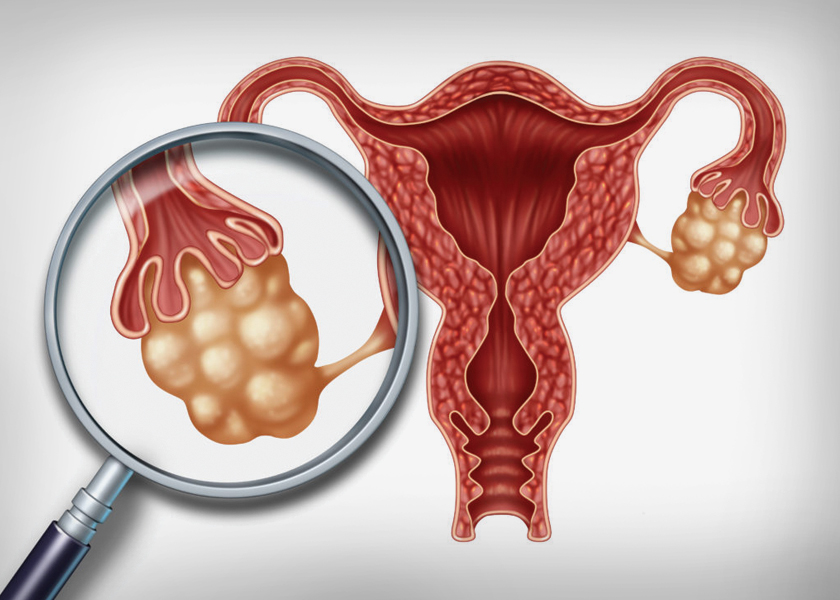

শরীরে হরমোনের ভারসাম্য বিঘ্নিত হলে পলিসিস্টিক ওভারি সিনড্রম হয়। অনিয়মিত ঋতুস্রাব হলে ডিম্বাণু নিঃসরণ ঠিকমতো হয় না। এটা এমন কিছু সমস্যার বিষয় নয়। তা ছাড়া, পলিসিস্টিক ওভারি হলেই যে অপারেশন করতে হবে- এমন কোনো দরকার নেই।

অনিয়মিত পিরিয়ড, পিরিয়ডের সময় পেট ব্যথা, অতিরিক্ত ব্লিডিং হওয়া, চিবুক-ঠোঁটের ওপরের অংশে অবাঞ্ছিত লোম, মোটা হয়ে যাওয়া, ওবেসিটি আক্রান্ত হওয়া, থাইরয়েডের সমস্যা হওয়া।

প্রেগন্যান্সি চাইলে ডাক্তারের পরামর্শ নিয়ে ওরাল মেডিসিন নেওয়া বন্ধ করতে হবে। এরপর যদি অন্তঃসত্ত্বা হতে কোনো অসুবিধা হয় তাহলে ডাক্তারের কাছে গিয়ে প্রয়োজনীয় চিকিৎসা করে নিলেই সমস্যার সমাধান হবে। অনিয়মিত ডিম্বাণু বেরনোকে নিয়মিত করে দিলেই ভবিষ্যতে মা হতে আর কোনও অসুবিধা থাকবে না। তবে পলিসিস্টিকের সঙ্গে ওবেসিটি থাকলে বিষয়টি জটিল হতে পারে। তাই মা হতে চাইলে আগে ওজন কমাতে হবে। এই রোগীদের প্রেগন্যান্সির সময় ব্লাড সুগার ও ব্লাড প্রেশার বাড়তে পারে। এছাড়া অন্য সমস্যা হলে সিস্টগুলিকে পাংচার (ড্রিলিং) করে দেওয়া হয়। তাতে সাময়িকভাবে ডিম্বাণু নিঃসৃত হতে পারে। তবে এখন এত আধুনিক ওষুধ বেরিয়েছে যে ড্রিলিং করার দরকার হয় না।